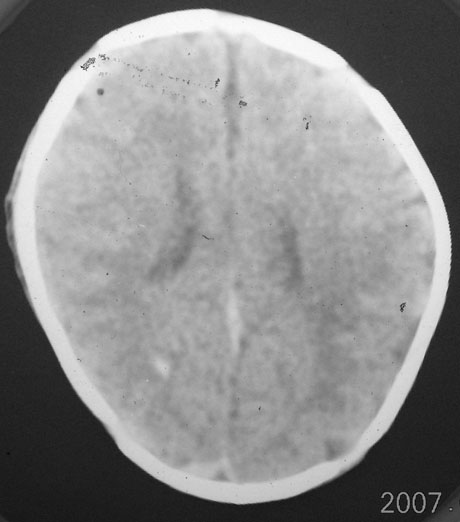

以下是引用rjg199343在2007-1-24 23:08:00的发言:[br]纵裂池、小脑幕、双侧脑室内高密度影,符合脑室、蛛网膜下腔出血。